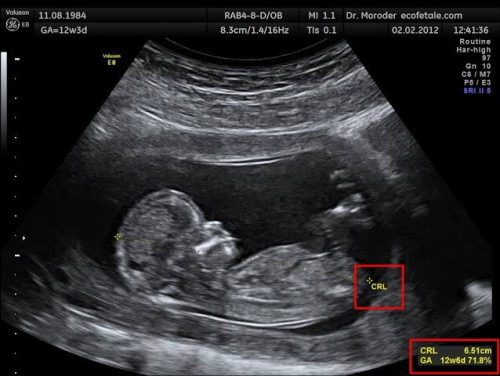

ใบอัลตราซาวด์

#ขอคำแนะนำหน่อยค่ะ ตรงนี้มันแฟบๆ ปกติมั้ยคะ เห็นของคุณแม่ท่านอื่นกลมๆแบบรูปที่1 เลยกังวล

ปกติค่ะ ขาเด็กเวลาอยู่ในท้องจะเล็กเพราะน้องต้องขดขางอเข่าจนคลอด คลอดมาจะเริ่มใหญ่ ยาว ยืดตามวัยค่ะแม่